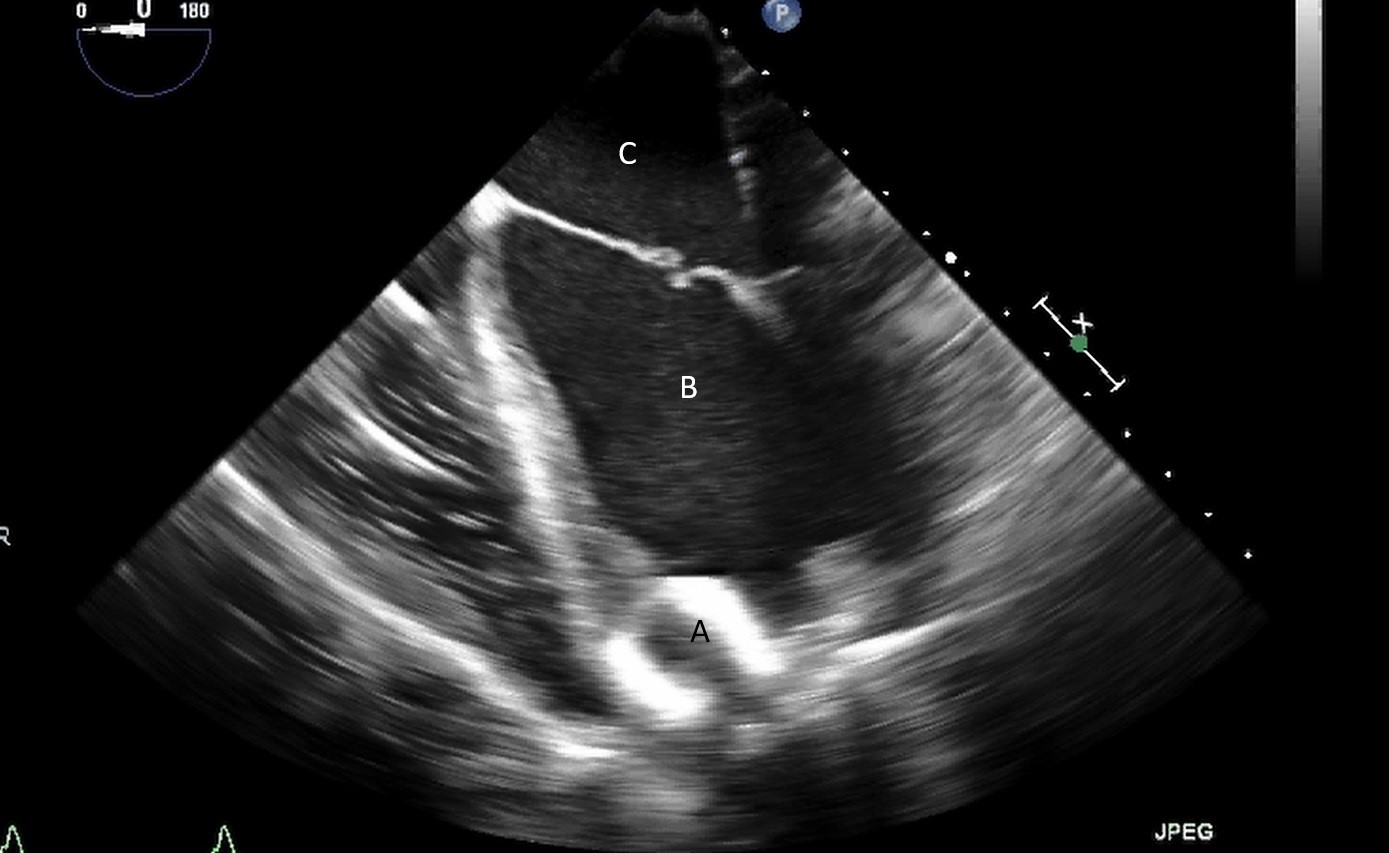

After initial access is obtained with a guidewire, TEE can confirm placement of the guidewire within the aorta and ensure there is no iatrogenic dissection from the procedure. The midesophageal long axis and 4 chamber views can be used to visualize the guidewire crossing of the aortic valve and positioning within the LV cavity. The wire tip should point towards the LV apex. Wire placement too deep within the LV can trigger ventricular arrhythmias and tethering of the mitral valve or subvalvular apparatus should be avoided as this can result in the inlet abutting the mitral valve or damage to subvalvular apparatus (Figs. 3,4) [13]. When the proceduralist is advancing the Impella over the guidewire, the best view to observe the device crossing the aortic valve is the midesophageal long axis view [13].

Impella (A) in the LV cavity caused disruption and damage to subvalvular apparatus resulting in flail segment (B) of the mitral valve.

Fig. 4.Impella (A) placement causing disruption and damage to subvalvular apparatus resulting in mitral valve flail (B) and mitral regurgitation (C).